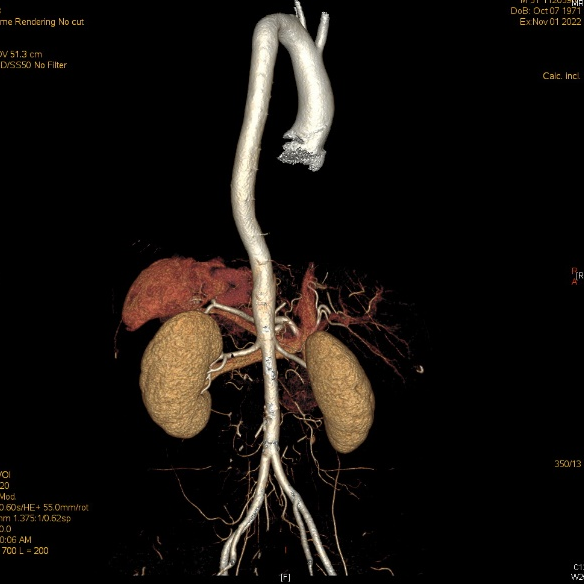

全主动脉+盆腔动脉增强CT

散在混合性斑块,管腔轻度狭窄;主动脉粥样硬化。